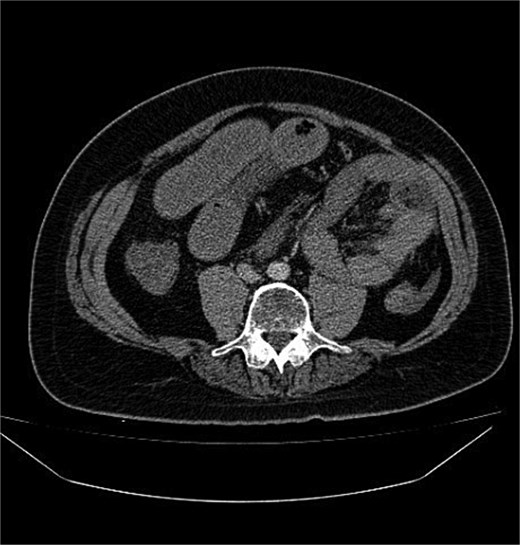

Abdominal radiography was non-contributory. Ultrasound demonstrated thickened small-bowel loops with inter-loop and minimal pelvic free fluid. Laboratory values showed WBC 20000/μl, Hb 15.4 g/dl, and platelets 417 × 109/l. Contrast-enhanced CT, despite limited field-hospital imaging capability, revealed a sac of clustered jejunal loops in the left upper quadrant beneath the superior mesenteric artery, consistent with a LPDH causing closed-loop obstruction (Figs 1 and 2).

Contrast-enhanced axial CT abdomen: cluster of jejunal loops in the left upper quadrant forming a sac beneath the SMV, with proximal small-bowel dilatation consistent with closed-loop obstruction.